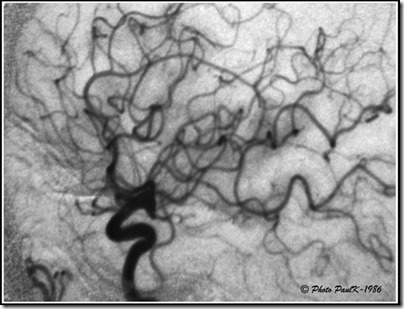

En radiographie, la technique du masque est surtout utilisée lors d’examens particuliers destinés à explorer le système artériel ou veineux.

Pour radiographier le système artériel ou veineux, il est nécessaire d’injecter un produit qui soit opaque aux rayons X.

C’est ce que l’on appelle communément, le produit de contraste.

Masque-ArterioAL’inconvénient de ce procédé est que les parties du corps les plus denses, les os en particulier, sont aussi opaques aux rayons X.

Cela rend donc la lecture et l’interprétation des radios plus délicates.

L’astuce photographique consiste dont à masquer sur le cliché, ces éléments indésirables.

Sur le cliché de droite, correspondant à une artériographie carotidienne, on ne voit pratiquement plus la structure de la boite crânienne ce qui permet d’obtenir une très bonne lisibilité du système artériel et veineux.

En prenant une radiographie de la zone à examiner avant toute injection, nous obtenons une image dont il est facile d’obtenir une image positive avec un film particulier (masque).   —> Ce qui est blanc devient noir et réciproquement.

Il sera alors facile de superposer ce masque au cliché obtenu, après injection du produit de contraste, pour obtenir une nouvelle image par soustraction, sur laquelle n’apparaîtront que les éléments attendus.